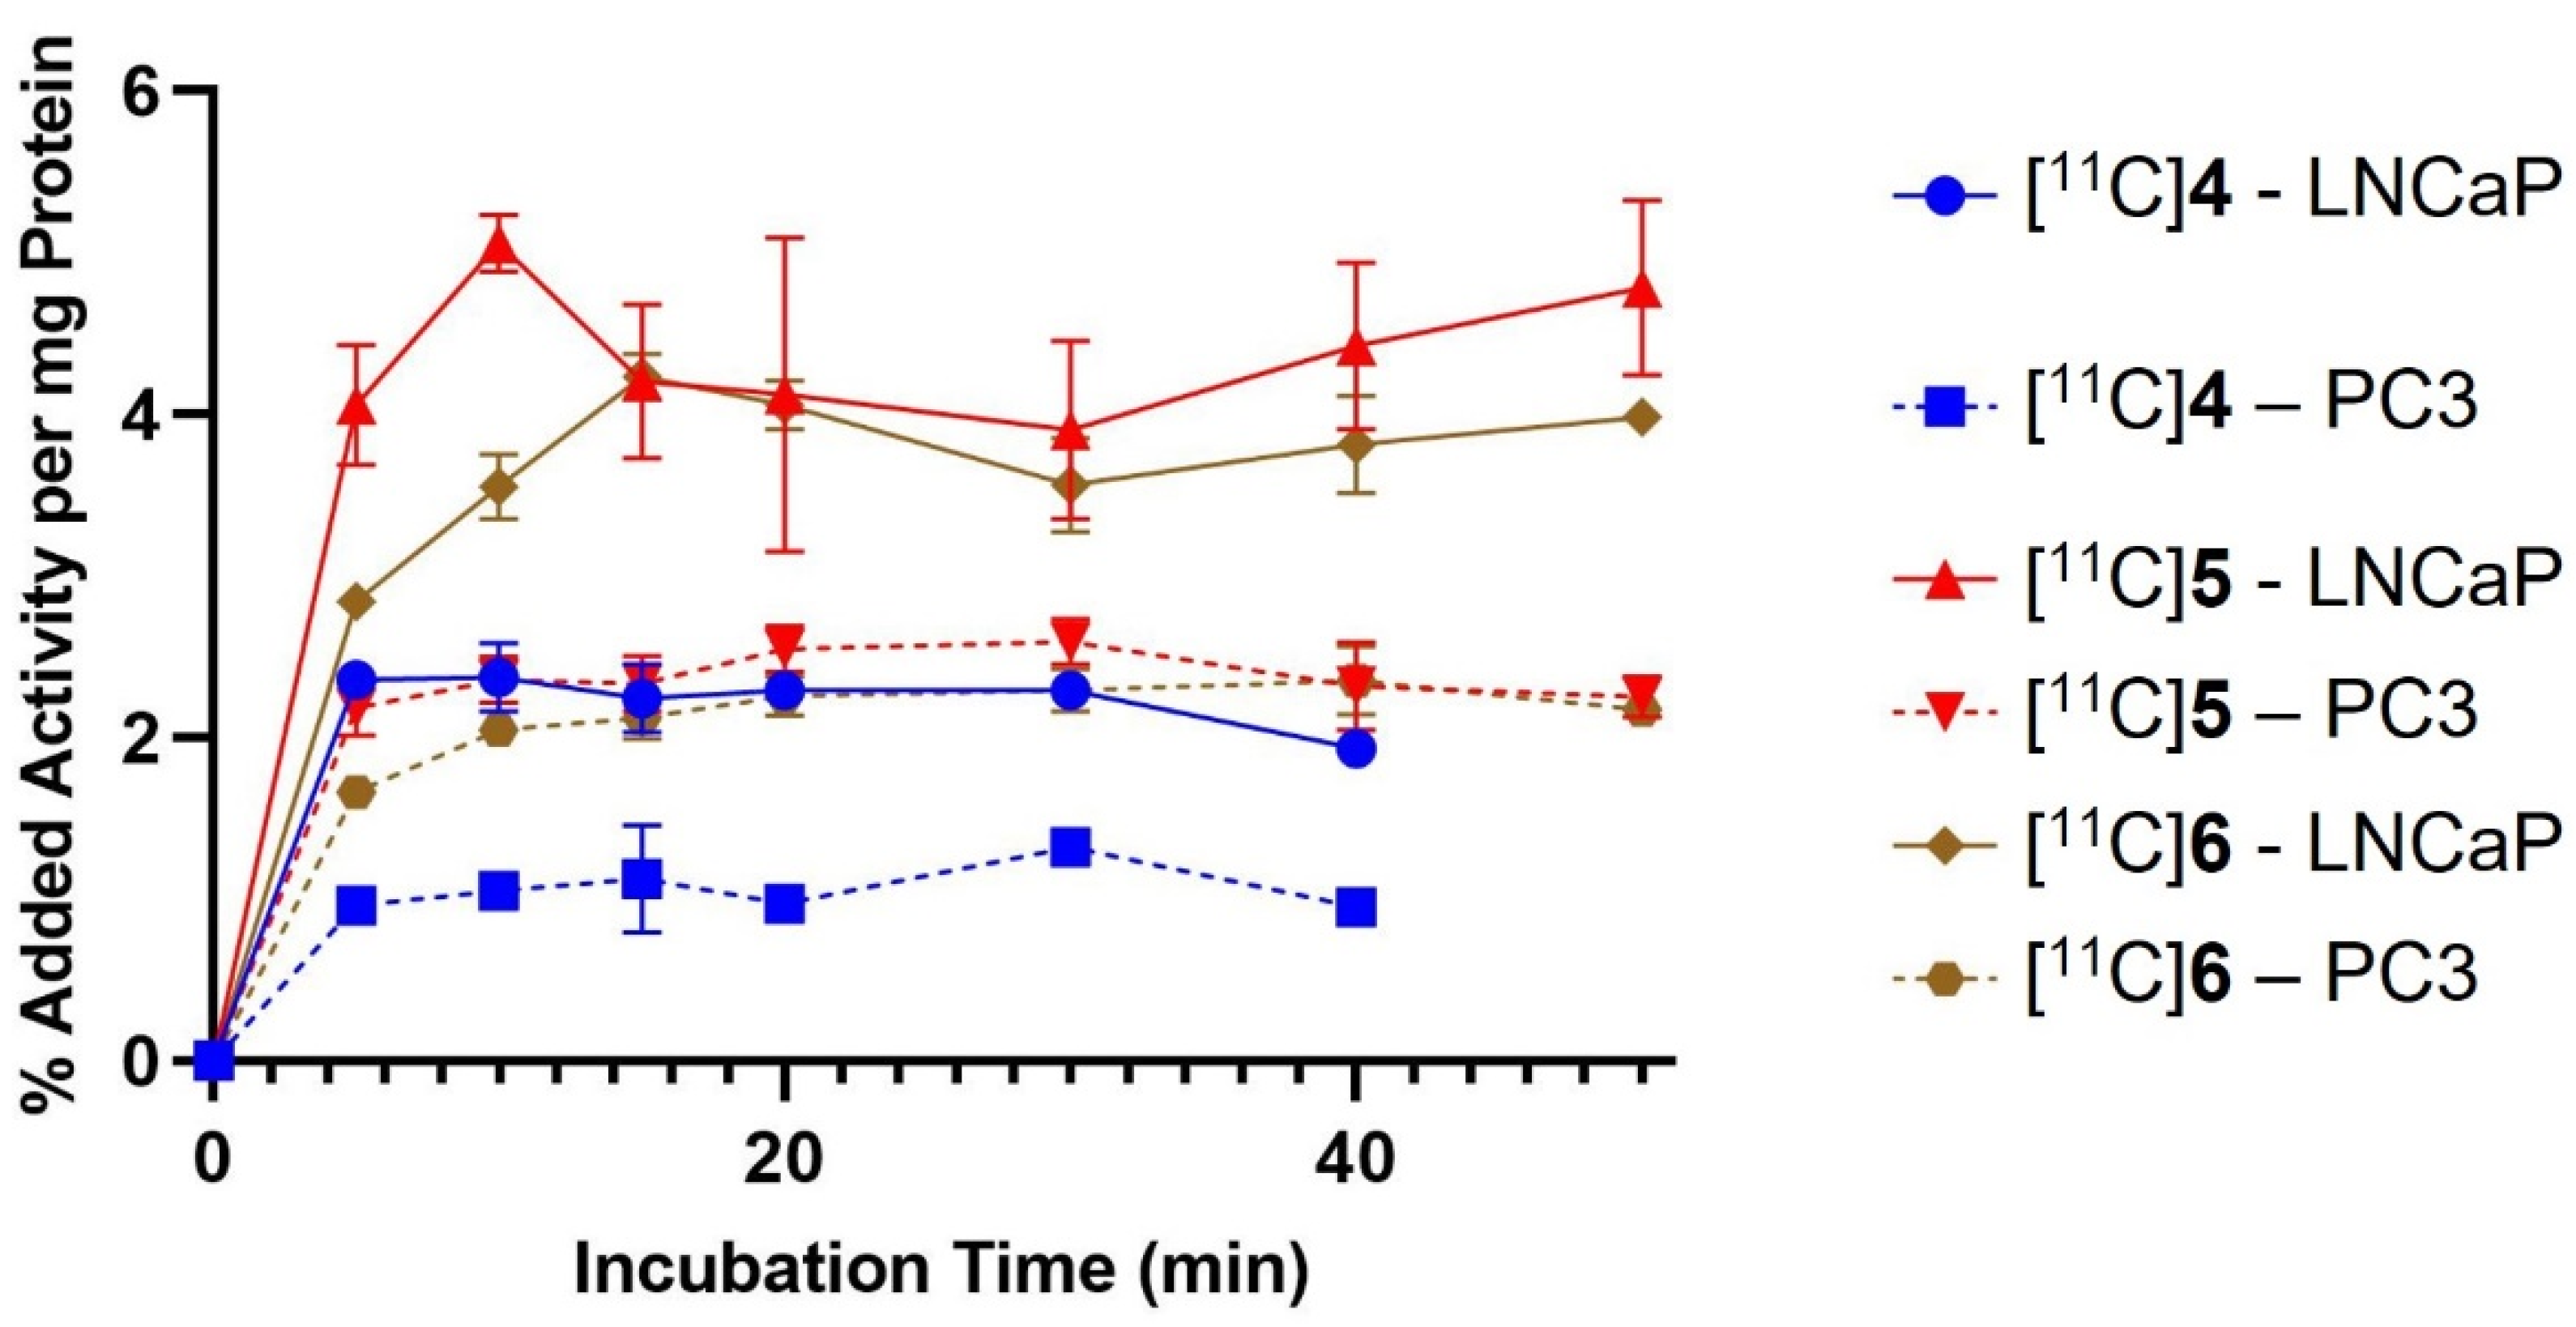

2.3. In Vitro Cell Binding

4.5. Binding to Prostate Cancer Cell Lines